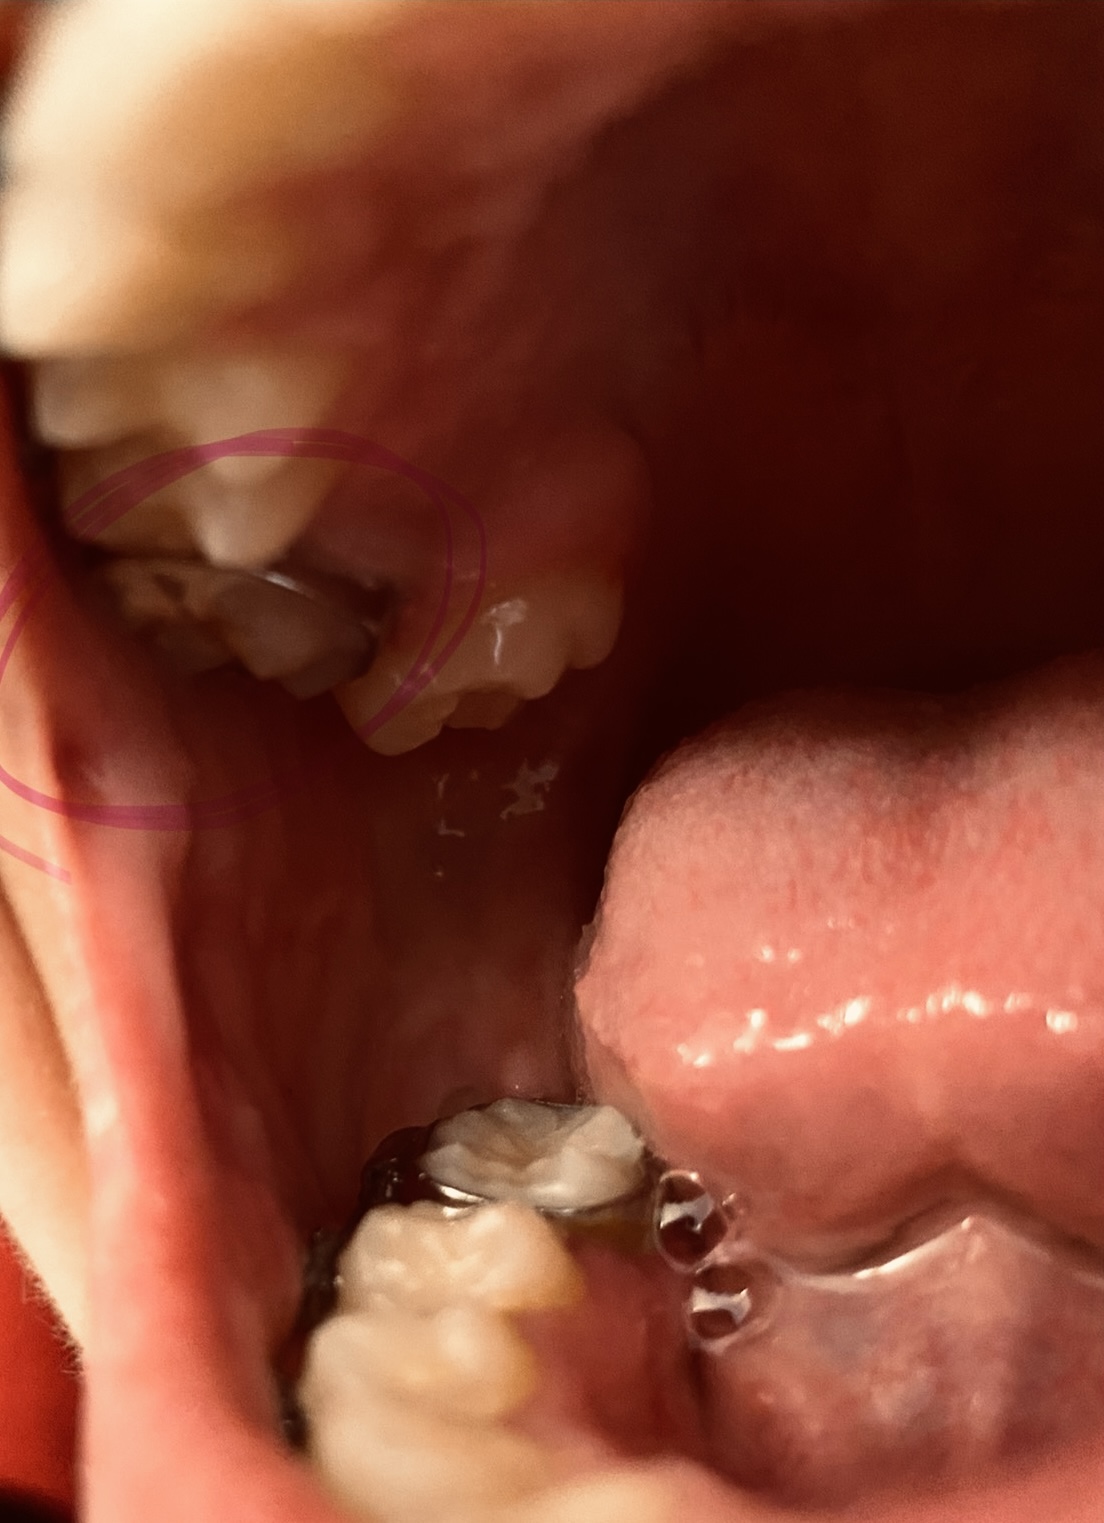

Good Morning, I have had braces for 20 months, but my orthodontist told me I would only need them 3 months! I basically was a relapse case. I had Invisalign in 2007-2008 to close a gap in my front teeth, and a permanent retainer was affixed to the back of my front four teeth to keep the gap closed. My current orthodontist finished my Invisalign case with a Howley retainer and elastics, after I initially had gone to a general dentist to start my Invisalign case. I was very pleased with my smile at the conclusion of my Invisalign case in 2008! In early 2016, my gap re-opened after my permanent retainer broke. It only took around two weeks for the gap to reopen upon the retainer breaking! I went to get the retainer repaired, and the gap had re-opened too wide for my orthodontist to close with finger pressure. Therefore, my orthodontist recommended a Howley retainer to try to remedy the problem. The Howley retainer closed the gap, but the top teeth did not meet well with the bottom teeth, causing malocclusion and 'hitting' of the two rows of teeth. Therefore, traditional metal braces were introduced as a solution. Again, my orthodontist said I would only need 3 months to conclude my braces treatment! It has now been 20 months! My braces treatment started in September 2016. At the three-month mark, I thought my bite was good, and my teeth were looking pretty good. About 5 months into treatment, I noticed there was a space forming in between my two left canine teeth. That caused the left side of my smile not to 'fit' together. It made my smile look uneven. My orthodontist tried to remedy this by making me wear elastics off on and on for over 6 months (between February 2017 - October 2017), but the space did not close as I liked by October 2017. They don't fit together much better now. At this time in October 2017, my orthodontist was talking about doing an impression! As much as I wanted to take my braces off at this time in October, after going 4 times the amount of time I thought I would be in braces (12 months at that time), I knew I would not be pleased with this result. Due to my dissatisfaction, My orthodontist then instituted other elastic configurations to see if this would help, but the desired result still did not happen. I visited other orthodontists for a second opinion on how to close the space better, and they recommended adjusting brackets to put more force on the teeth at better angles to make them fit. I mentioned moving brackets to my orthodontist. However, for some reason, my orthodontist was against moving brackets, always saying "I don't need to do that. I can bend the wire." She insisted that only young orthodontists use the adjusting of brackets as a method, particularly because that is how they were taught, and they aren't familiar with bending wires, as she, an older orthodontist, is familiar. She said that younger orthodontists aren't trained to bend wires now, as she was taught. My orthodontist finally begrudgingly moved the bracket on my top canine higher on the tooth, around early March 2017, after I asked for a third time. I did not want the bracket moved higher, but lower, as I wished to tilt the crown of the tooth more upward. However, my orthodontist did it her way. Her moving the bracket higher caused the top canine to come down in an unsightly fashion, almost at an angle. It also exacerbated the situation, as it made the space between the canines much bigger. It stayed like this over two months inexplicably (this is when I started to get other second opinions), and she just closed the space in late April, with an adjustment. The photo I have posted is how my teeth look now. I wanted to post photos that show change from the beginning until now, but there seems to be one-photo limit on this site. In the current photo, I still don't think my left canines meet well, and the top canine still comes down at a less than aesthetic angle and sort of just overlaps the bottom canine, rather than 'fitting' it. Another issue that makes my smile look uneven is that my left and right incisors are not level with each other. You can see that in the photo. My orthodontist has not been able to successfully address this either. She has tried to use a powerchain to bring the bottom teeth inwards, so the top teeth can come down more, and thus the left incisor can be moved down, but the powerchain has not worked. To sum up, my orthodontist's 'bending of the wires' has not moved my teeth into the desired position. It's really as if there has been hardly any real noticeable movement from February 2017 to now May 2018. I would think from all of that time to perfect, my teeth would look amazing now, but they don't. If you look at my photo, the spaces mentioned above make the left side of my teeth look a little jagged and 'open'. The right side of my smile is well spaced, and 'closed' from the front. What I mean by 'closed' is that you only see white teeth connected, and no spaces or fault lines. However, there are still spaces in between teeth on the left side, namely between the left incisor and the left front tooth at their bases, and the left canines are not meeting flush, but overlapping moreso. I simply want the left side of my smile to match the right side of my smile, particularly from the front. I must note that from my side profile, there are still some fault lines from the side, where teeth don't seem to meet the best way as well. However, I could be willing to deal with this if the teeth can be fit better from the front. My orthodontist doesn't seem to have the ability to move brackets strategically and does not seem flexible enough for me as a patient. It feels like every time I have an appointment, she is just doing trial and error, with no real conclusive plan on how to solve my problem. This has been going on for over a year in regards what I felt were easy problems to solve! I am thinking of changing to an orthodontist whom I consulted for a second opinion, whom uses more advanced techniques than my current orthodontist. I am beyond frustrated and fatigued of wearing braces. I am an older man, at 38 years old, and only agreed to get braces because I was told my initial issues (closing a gap between my two front teeth, and re-positioning my bottom teeth) would only take 3 months to treat, and there were no other issues. My orthodontist has non-urgently taken nearly 8 times that amount of time, only to leave me with dissatisfaction. I would like to go to another orthodontist. However, I don't want to pay out more money if this is an issue that can't be remedied any more than it already has. What do you recommend from looking at my picture? The other orthodontist whom I consulted for a second opinion, recommended wearing 'inside-out' rubber bands to 'tuck' the top-left canine in better and have it meet better with the bottom, and then proceed with bracket adjustment to finish the space closure for a better fit. To allow the left incisor to come down more to be level with the right incisor, they recommended potentially doing interproximal reduction on the lower four teeth to create more room to angle them inwards, which would allow the top row to come down more and look more even with the bottom (so my smile would look more even overall). Thus, the left incisor could be brought down more and and be positioned level with the right one, without malocclusion and hitting on the bottom teeth, which has been a problem as well. She said the interproximal reduction would also allow the top two front teeth to rest better on the bottom teeth and not hit too hard, which would help my gap stay closed better than the current position would. This would help avoid a second relapse. Do you think these methods and suggestions from the second orthodontist could work to fix my issue(s)?